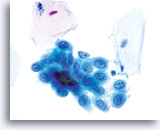

在传统的巴氏涂片上,细小的异常细胞通常会与 HSIL 相伴出现;这些细胞通常会被包裹在粘液中,或“隐藏”在背景物质内的细胞团内。由于在采用 ThinPrep 系统时,粘液和细胞碎片会经过分散处理,因此由该系统处理的标本会看起来有所不同。在使用倍镜读片时,细小的 HSIL 细胞会以单个细胞或以小细胞团的形式,在细胞的沉积背景中“凸显”出来。这些细胞应能提醒您:应更加密切地关注所呈现出的细胞物质,并查找是否有更多可供诊断的高度上皮细胞团。只要在低倍镜下看到这些细小的单个细胞或细胞团,就可在高倍镜下对这一部分玻片进行“筛查”。ThinPrep 系统的分散处理流程不会使真正的上皮细胞团发生破碎(因为高度病变存在异型性),并将会呈现出更多的单个细胞,注意到这点是至关重要的;这些是寻找病变细胞的“线索”。

在玻片上,并不是每个不良细胞都会呈现出这些三维结构的异型性;但是,在这些玻片上,这些异型性至少会在一些细胞中较为明显。显然,染色质量直接关系到是否能够看到胞核“内部”。(与传统的巴氏涂片相比,所有的 ThinPrep® 涂片检测都使得细胞变化更为明显;但如果对反应物进行过度染色,或有轻微腐败,都将对这种最为重要的评估标准造成直接影响)。此外,与细胞凹陷或简单的褶皱(会达到胞核的全部宽度,具有“相似本体”,并会造成一定的难度)相比,这些三维结构的缺陷应该是不对称的。由于这些胞核的三维异型性能够得到放大,因此能够为 HSIL 诊断提供依据。